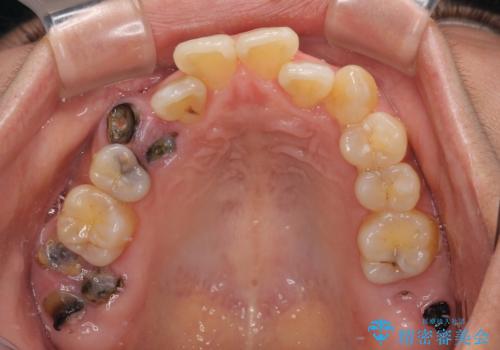

- 前歯などに、むし歯でボロボロになった歯があるとのことで来院された患者様です。

むし歯により歯冠が崩壊してから長いこと経過しているとのことで、歯を失ったことによる他の歯への影響はあまりないと判断されたため、審美領域である上顎前歯部のみにインプラント補綴治療を行うこととしました。

2本の歯が前後に重なった状態でむし歯となっていたので、抜歯後に歯肉や骨の状態が落ち着くのを待ち、インプラントを埋入することとしました。